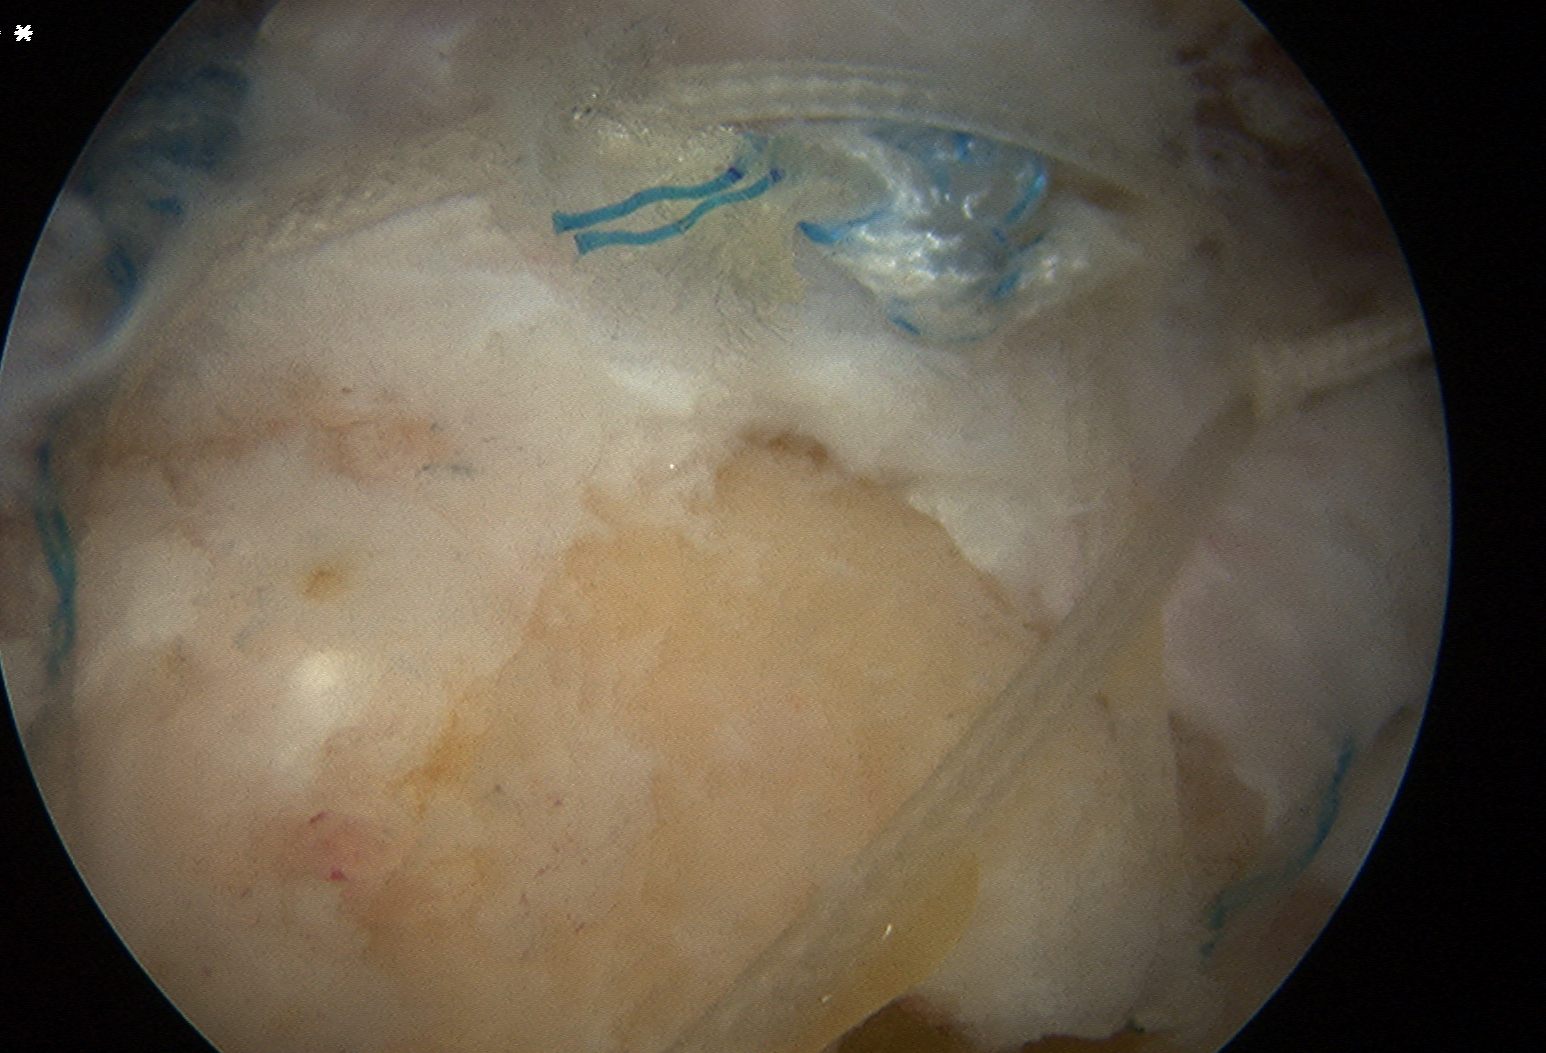

Repair

Large U shaped tendon

- insert margin convergence sutures

- put camera in lateral portal

- insert posterior cannula over switching stick

- anterior and posterior bird beaks

Place medial row anchors

- anterior first

- insert 18 G spinal needle and ensure good angle

- just medial to articular cartilage

- stab incision

- insert 5 mm anchor

Pass sutures in lateral margin cuff

- camera posterior

- elite / scorpion / concept suture passer via lateral portal

- pass sutures through cuff anterior to posterior

- retrieve sutures through anterior portal

- retrieve via anterior portal

Repeat with posterior anchors

Tie sutures

- posterior to anterior / anterior to posterior